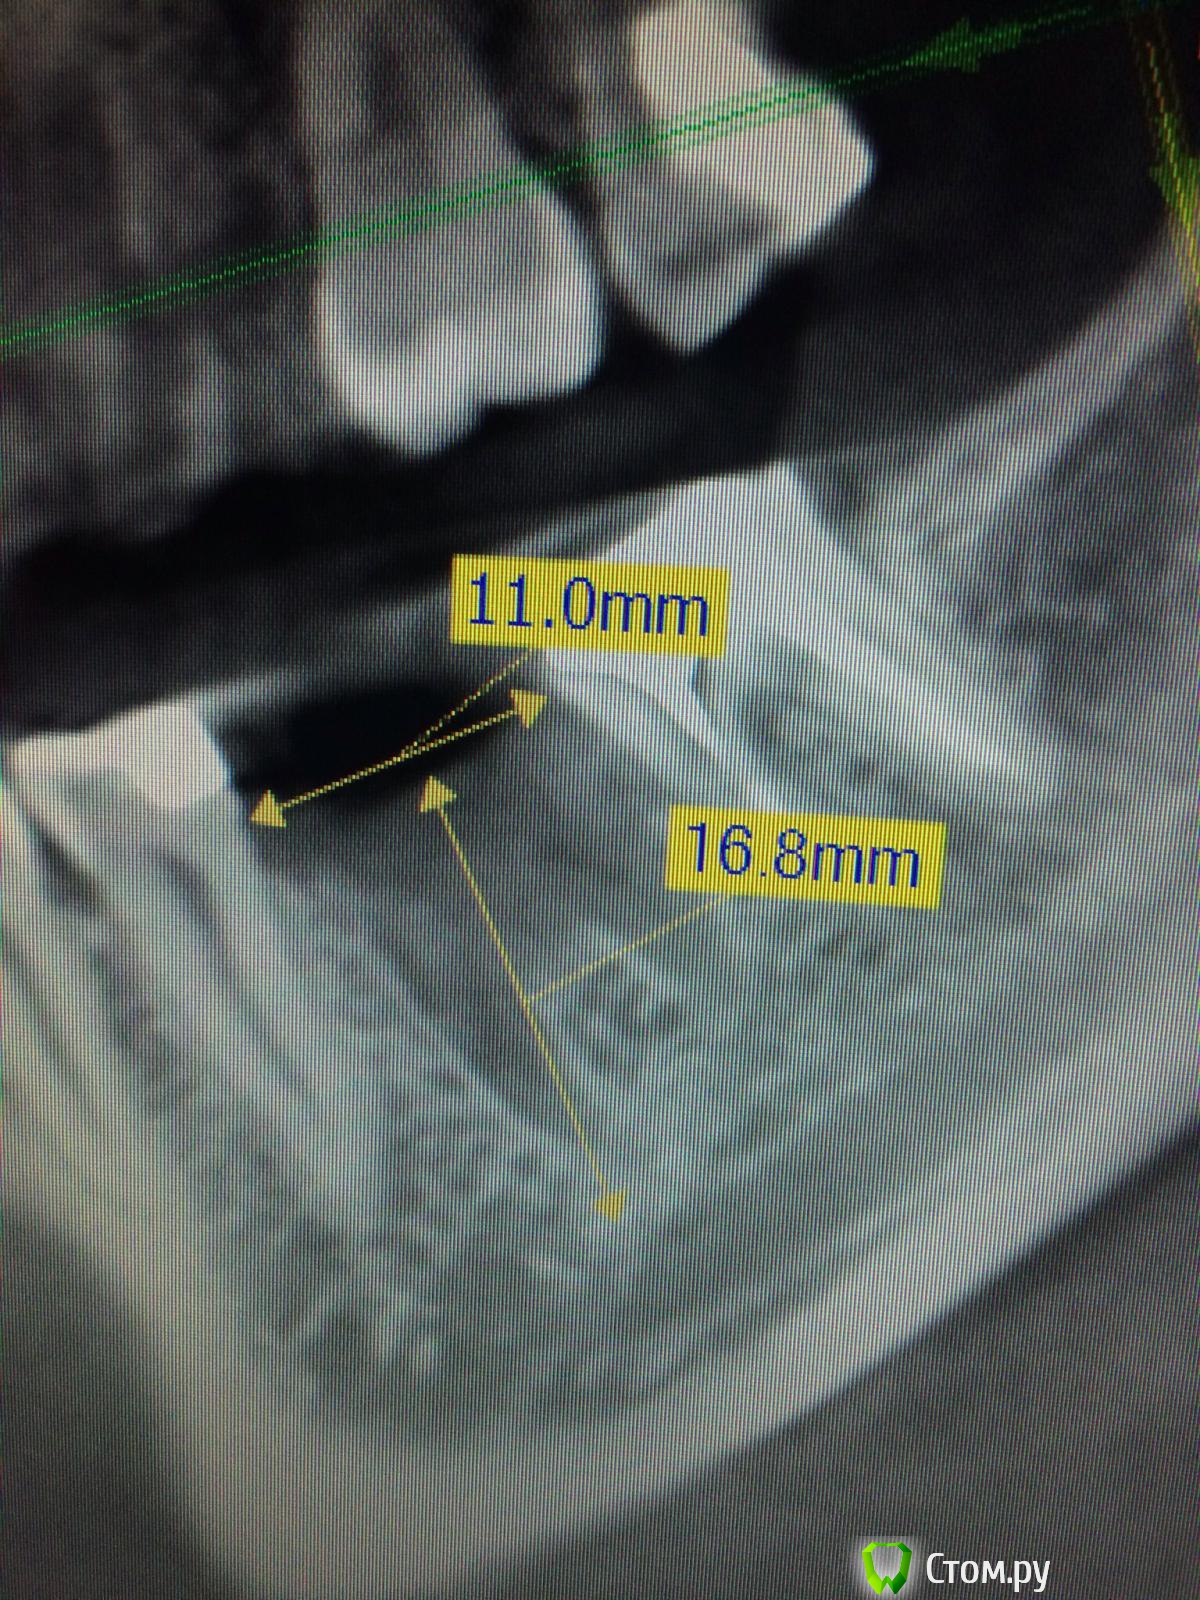

Vadim09 Опубликовано 8 октября, 2014 Поделиться Опубликовано 8 октября, 2014 Зуб удалял в начале июля, как думаете есть тут кость, потребуется подсадка кости и мембраны или нет? Ссылка на комментарий

Дмитрий Никитюк Опубликовано 8 октября, 2014 Поделиться Опубликовано 8 октября, 2014 С мягкими тканями понятно. Они заживают за 6-8 недель, мы все это знаем и видим, в отличие от состояния кости. Какой объективный критерий есть для того, чтобы со всей уверенностью сказать, что вертикальная потеря костной ткани уже произошла? Т.е. пришёл пациент и вообще не помнит, когда и как ему удаляли зуб. Когда будем ставить имплантат и почему? Кстати, на снимке топикстартера видно, что ставить ещё немного рано... Ссылка на комментарий

Vadim09 Опубликовано 8 октября, 2014 Автор Поделиться Опубликовано 8 октября, 2014 1. сам удалял зуб или нет2. мягкие ткани через 2 мес1. Сам2. Мягкие ткани еще не видел, в пикассо делала, на почту прислали, в пятницу должна прийти на осмотр и мб сразу поставлю нобель СС 4.3 *10, на всякий купил кость и мембрану Ссылка на комментарий

Дмитрий Никитюк Опубликовано 8 октября, 2014 Поделиться Опубликовано 8 октября, 2014 1. Сам 2. Мягкие ткани еще не видел, в пикассо делала, на почту прислали, в пятницу должна прийти на осмотр и мб сразу поставлю нобель СС 4.3 *10, на всякий купил кость и мембрану Откуда такая спешка? я ведь это видео не случайно Вам сюда поставил. там через 3 месяца картина очень похожа на Вашу, только немного лучше. Именно поэтому я ещё 2 месяца подождал. По поводу более-менее объективного критерия, kriokov прав - для того чтобы не сомневаться, лучше дождаться образования замыкающей пластинки. Она чётко видна на видео на постоперационном снимке. Или вот ещё, можете посмотреть: http://s020.radikal.ru/i701/1410/14/27daab7c61aa.png И сравните с Вашими снимками: http://s005.radikal.ru/i212/1410/d3/ed89f99cbcb1.png Если Вы будете использовать кпм и мембрану, то Вы потеряете минимум полгода, а пациент потеряет и время, и деньги. 2 Ссылка на комментарий